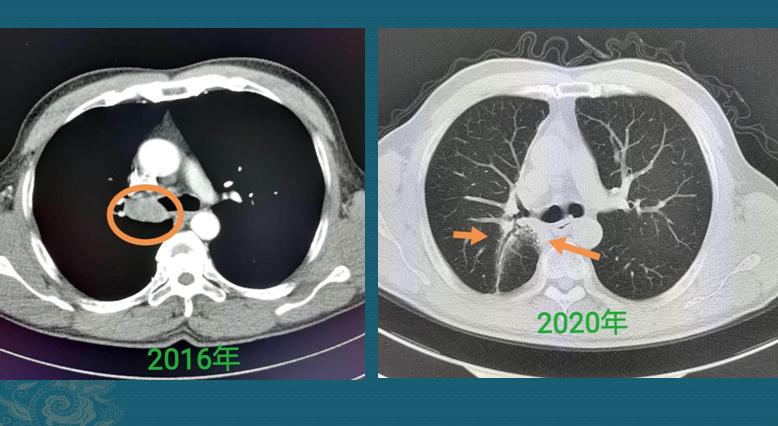

这是一位成年男子,干咳一周发现右侧肺癌,2.2厘米,支气管镜淋巴结穿刺以及痰液检查,明确为浸润性肺腺癌,伴有多发转移。

已经无法做根治性手术,选择放弃治疗听天由命,结果仅仅过了8个月,复查CT显示肿瘤增大到接近8厘米,速度非常快: